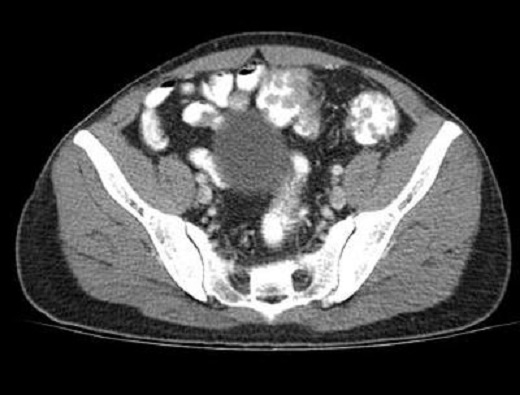

Aspect radiologique polypoide multiple du

colon . Image du polyp ét tré nombreuse et s'etendre

le long du colon ascendant , transverse et

descendant . Image radilologique TDM a lavement

baryte du polyp dans ce cas est multiple a

hypo-dense et s'etendre le long de arcade colique .

Maladie polypoide du colon |

Même cas en coupe TDM

axiale a travers L2, L3 . Image du polyp dans ce cas

est multiple polypoide a hypodense s'etendre

le long du colon transverse . Image

radiologique TDM du colon avec lavement opaque du

colon . |